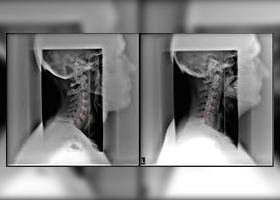

Cervical spine surgery refers to surgical procedures performed on the cervical spine, which is the portion of the spine located in the neck.